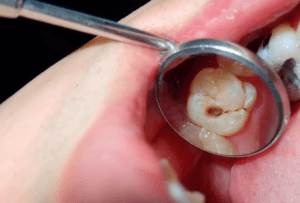

سقوط حشوة الأسنان هو انفصال الحشوة التي وُضعت سابقًا لعلاج تسوس أو كسر في الضرس أو السن، بحيث تترك تجويفًا أو فراغًا مكشوفًا داخل السن. يحدث سقوط حشوة الأسنان عادة نتيجة تآكل مادة الحشوة مع الوقت، أو الضغط الزائد أثناء المضغ، أو كسر في جدار السن، أو تسوس جديد حول الحشوة القديمة. عندما تسقط الحشوة يشعر المريض غالبًا بحساسية أو ألم عند تناول الأطعمة والمشروبات الباردة أو الساخنة أو الحلوة، وقد يلاحظ وجود ثقب أو تجويف خشن بلسانه في مكان الحشوة. يعتبر سقوط حشوة الأسنان حالة شائعة لكنها لا يجب إهمالها، لأن بقاء السن مكشوفًا يعرضه لدخول البكتيريا وازدياد التسوس والتهاب العصب، ما يستدعي مراجعة طبيب الأسنان بسرعة لإعادة حشو السن أو استبدال الحشوة التالفة بحشوة جديدة تناسب حالة الضرس وتضمن حمايته على المدى الطويل.

مع مرور الوقت قد يتآكل حشو الأسنان نتيجة الاحتكاك المستمر بالطعام وقوى المضغ، ما يؤدي إلى تكوّن فراغات مجهرية بين الحشوة وسطح السن. هذه الفراغات تسمح بتراكم بقايا الطعام والبكتيريا وحدوث تسوس تحت الحشو، وهو أحد أهم أسباب سقوط حشو الأسنان بشكل مفاجئ. عند استمرار التسوس تحت الحشوة يضعف جدار السن الداعم لها، فتفقد الحشوة ثباتها وتنخلع جزئيًا أو كليًا. الكشف الدوري عند طبيب الأسنان يساعد على اكتشاف التآكل والتسوس تحت الحشو مبكرًا قبل أن يصل الأمر إلى سقوط حشوة الأسنان بالكامل.

عند سقوط حشوة الأسنان يلجأ طبيب الأسنان إلى مجموعة من الخيارات العلاجية الدقيقة لإصلاح الضرر أو استبدال الحشوة بما يضمن حماية السن على المدى الطويل وتحقيق أفضل نتيجة جمالية ووظيفية. يبدأ التقييم بفحص سريري وأشعة لتحديد مدى تسوس السن أو كسر أجزاء منه، ثم تنظيف التجويف جيدًا من بقايا التسوس أو الحشوة القديمة قبل وضع حشوة جديدة ملائمة من حيث النوع والحجم. في كثير من الحالات يُفضل استخدام حشوات تجميلية بلون السن (الكومبوزيت) خاصة في الأسنان الأمامية أو المناطق الظاهرة عند الابتسامة، بينما قد تُستخدم الحشوات المعدنية أو الأملغم في الأضراس الخلفية التي تحتاج لتحمل قوى المضغ العالية. إذا كان سقوط حشوة الأسنان مصحوبًا بتضرر كبير في بنية السن أو كسر في الجدار الخارجي، فقد يوصي الطبيب بعمل تاج (تلبيسة سن) لحماية السن بالكامل ومنع تعرضه للكسر مستقبلاً. أما في حال وصول التسوس إلى عصب السن مع ألم شديد أو خراج، فقد يتطلب الأمر علاج عصب متبوعًا بحشوة دائمة أو تاج، لضمان استقرار السن ووقف انتشار الالتهاب. اختيار الخيار العلاجي الأنسب لاستبدال أو إصلاح الحشوة يعتمد على تقييم الطبيب لحالة السن، عمر المريض، موقع السن في الفم، والميزانية المتاحة، لذلك من الضروري مراجعة طبيب الأسنان فور سقوط الحشوة وعدم الاعتماد على حلول منزلية مؤقتة قد تزيد المشكلة سوءًا.